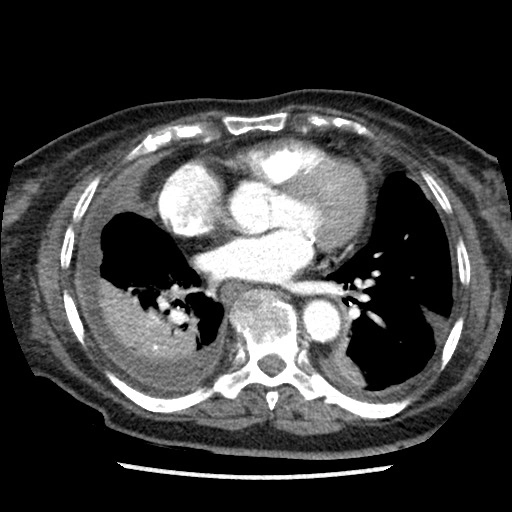

Ung thư tuyến giáp thể nhú (Papillary thyroid carcinoma)